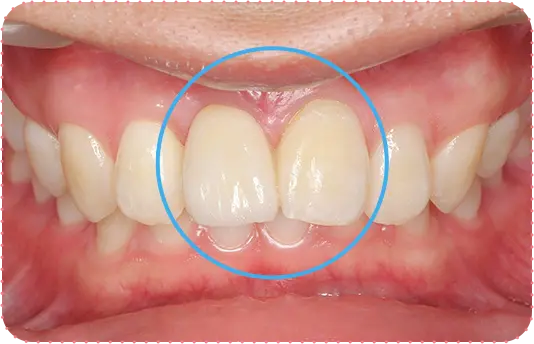

Before

After

主訴

上の前歯が長くて気になる

治療期間

9か月

治療費

30万円

治療内容

右上1番を小矯正治療にて歯茎を増やし、右上1番と左上1番をセラミッククラウンにて修復

治療のリスク

咬み合わせによっては、セラミックが欠ける可能性があります。